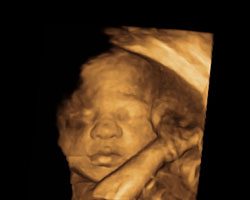

Continuamos a avançar! Queres ver o aspeto aproximado do bebé durante esta semana? Em seguida, mostramos-te a imagem de uma ecografia e vídeo para que possas ver o bebé em movimento. Apaixona-te!

Ecografia de 29 semanas